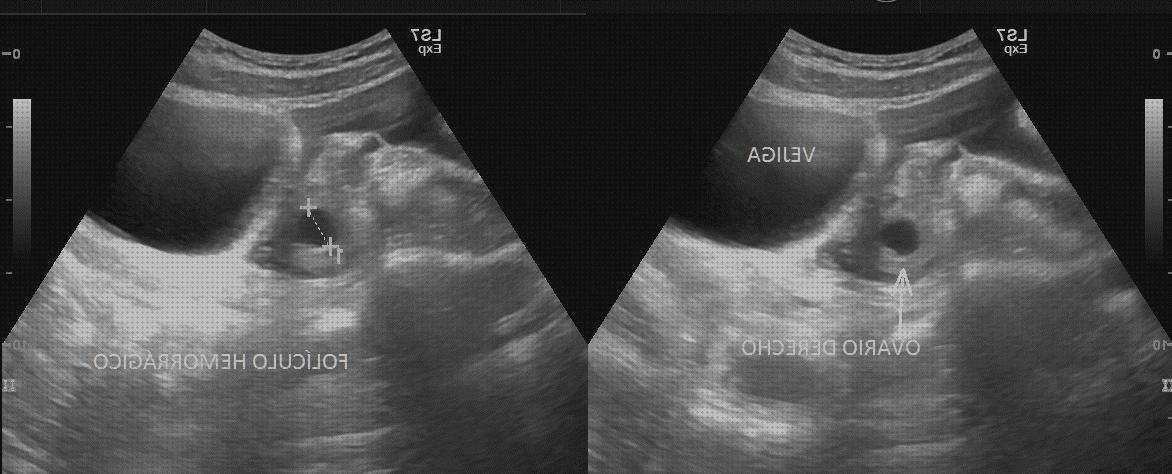

Opinión de un comprador: Muy fundamental pero ideal para comenzar en ecografía. Explica las técnicas para hacer buenos cámara ecograficos y las patologías más comunes de cada órgano. Incluye mucha foto.

Opinión de un comprador: Es precisamente lo que requeria. Enorme calidad de fotos con excelentes explicaciones de que es lo que ves. Te asiste para conocer y entienden las imágenes que ves en el ecografo